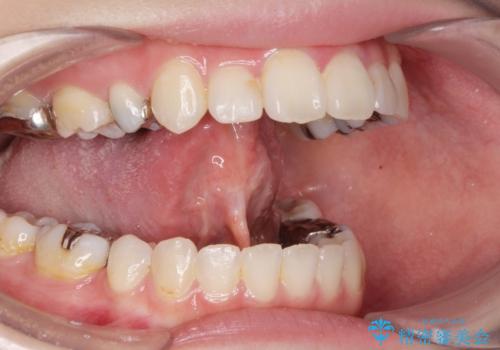

- 舌が動かしにくく、過去に舌小帯切除を行ったがあまり切除されず後戻りをしたため、舌小帯切除を希望されました。

舌小帯の形成術を行い、舌の可動域を広げました。